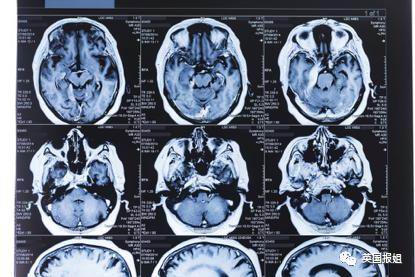

这不是玄幻故事,而是一位新冠重症患者.Kim.Victory,在.ICU(重症监护室)时脑海中会产生的幻觉。这种陷入恐怖片般的体验是很多新冠病人都有的症状,它被称为.ICU.谵(zhan)妄症。

Kim.Victory.几个月前感染新冠,成为一名重症患者,被送入.ICU。在治疗期间,由于使用大量镇静剂,她患上了.ICU.谵妄症。

看上去虽然和噩梦差不多,但病人在产生幻觉时并没有睡着。Victory.因为幻觉的骚扰常常使她难以控制情绪,以至于有天晚上,她突然拔掉了呼吸机的呼吸管。

还有一次,她从椅子上摔下来,倒在重症监护室的地板上。这一切的始作俑者就是.ICU.谵妄症。

美国精神病学会(APA)定义其为一种急性脑功能的意识和认知障碍,又称.ICU.精神病、ICU.综合征、急性精神错乱状态、急性脑衰竭等。是.ICU.危重患者的常见病症,80%.的.ICU.患者都有过这样的症状。

简单来说,谵妄患者的精神状态会突然变化,或突然陷入困惑,持续时间由数小时至数天。